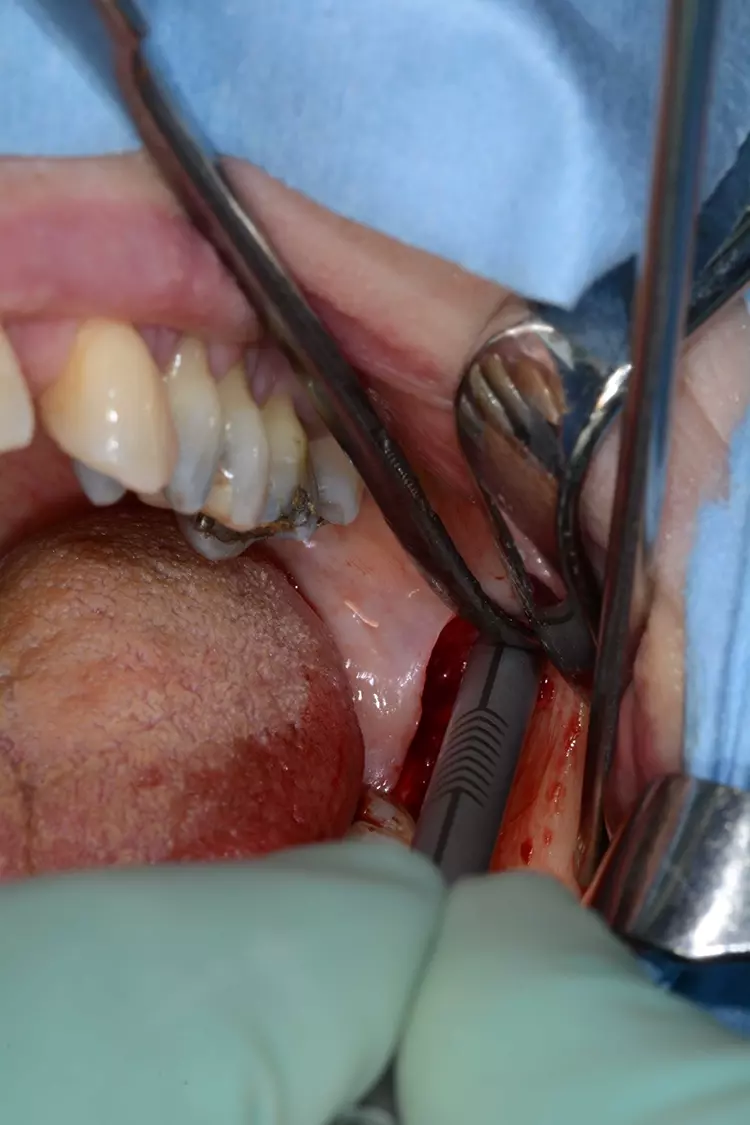

Chirurgisches Protokoll – 1. Sitzung

Der Wundbereich wurde mit monofilem, nicht resorbierbarem Nahtmaterial durch eine Kombination aus Rückstich- und Einzelknopfnähten vernäht (Abb. 6). In der klinisch postoperativen Kontrolle nach vier Wochen zeigte sich die Wundheilung komplikationslos (Abb. 7).